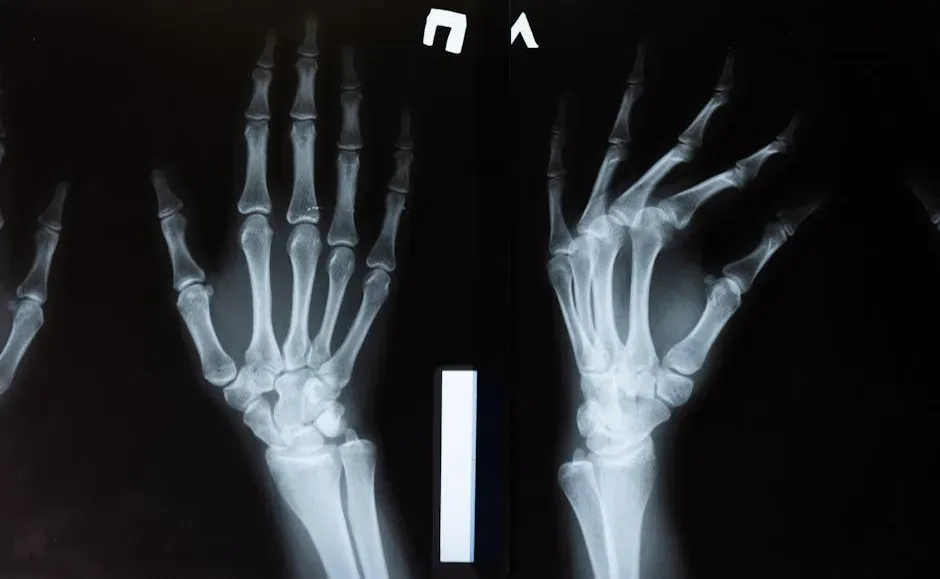

We tend to think of bones as rigid, unchanging frames, but they’re actually living tissue under constant renovation. Specialized cells called osteoclasts break down old or stressed bone, while other cells called osteoblasts build new bone in its place, like a demolition and construction crew working side by side. Even without a fracture, your skeleton is constantly being reshaped based on the forces you put on it, which is why regular movement and weight-bearing exercise matter so much.